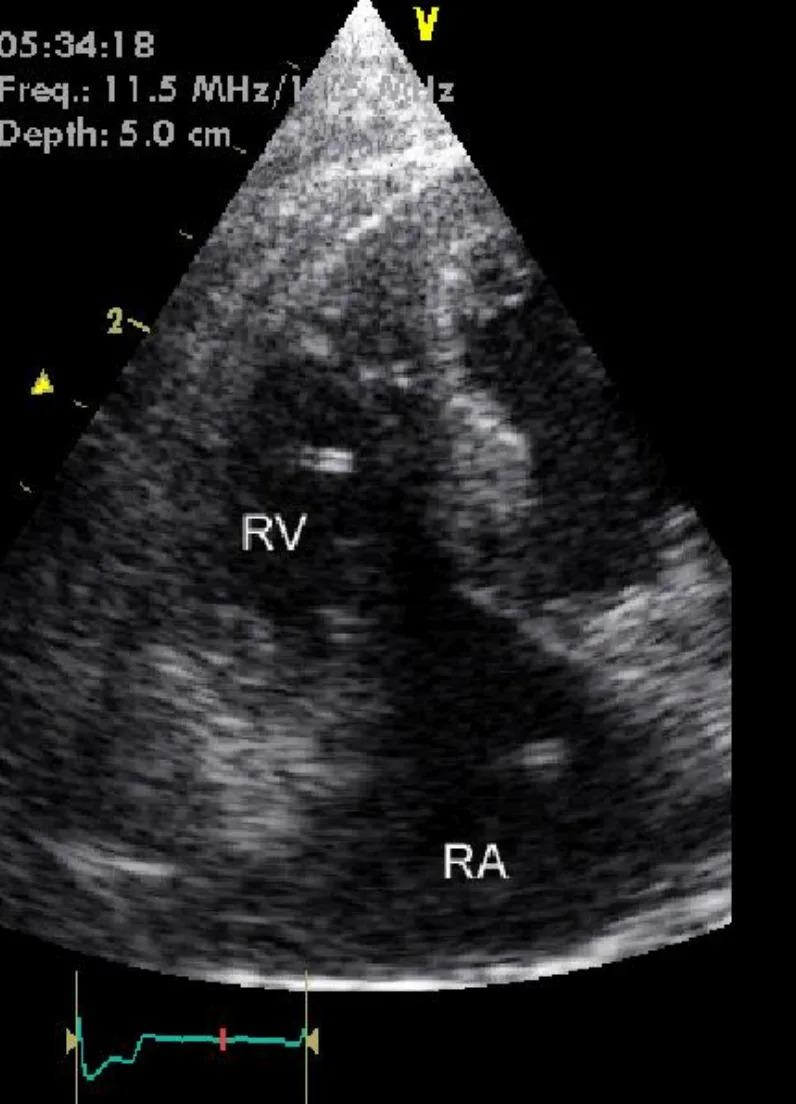

Echocardiography can be a sensitive means for detecting heartworms but often requires a skilled ultrasonographer. Adult heartworms in cats are smaller than those found in dogs and typically reside in the pulmonary vasculature where imaging is difficult. Heartworms resemble hyperechoic parallel lines and may be identified in the pulmonary arteries, right ventricle, across the tricuspid valve, or within the right atrium.

Echocardiography was performed (D); the image is a left parasternal view of the right atrium (RA ) and right ventricle (RV ). Note the hyperechoic parallel lines representing heartworms in the RA and RV.